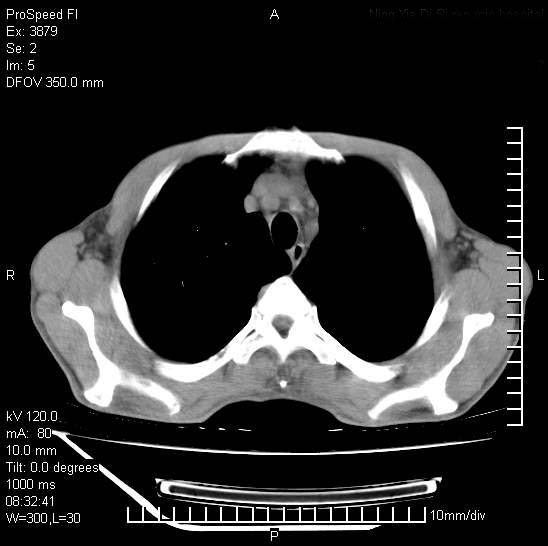

以下是引用312nanyang在2008-6-6 15:12:00的发言:[br]基本支持楼主意见[br]疑问?左下肺支气管旁的软组织(16层)密度怎么解释?淋巴结还是斜裂胸膜增厚所致?能否增强进一步检查